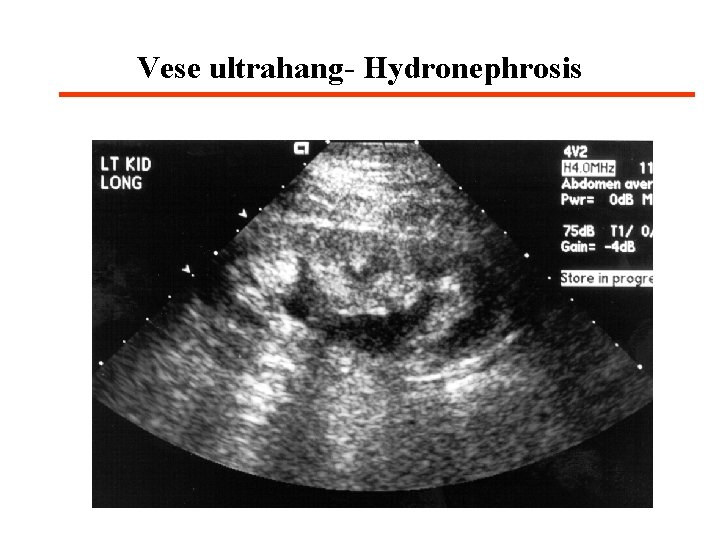

Postrenális AV 4 Vizelet elvezető rendszer obstrukciója vizelet pangás és hydronephrosis · Obstrukció szintje szerint - Felső traktus (uretherek) - Alsó traktus (hólyagkimenet, urethra) · Obstrukció foka szerint - Részleges - Teljes

Postrenális AV klinikai megjelenése 4 Diagnózis · Karbamid/kreatinin arány> 20: 1 · Vizelet üledék nem kórjelző · Változó vizelet kémia · Ürítés utáni hólyag retenció - > 100 m. L mutatja az ürítési diszfunkciót · Radiológiai eljárások - Ultrahang - CT - Nucleáris medicina - Retrográd pyelographia - Antegrád nephrostoma

Vese ultrahang- Hydronephrosis